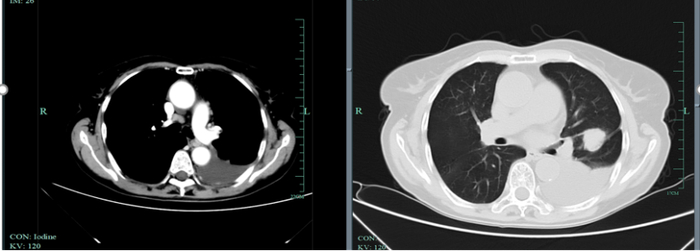

疗效评估:复查时原发灶较基线时明显缩小,达到深度缓解,并在随后治疗中持续缓解长达39个月。

上述病例为初诊转移性NSCLC患者,在基因检测明确BRAF V600E突变后,接受达拉非尼+曲美替尼一线治疗。在服药1月余后复查肺部CT,原发灶较基线时明显缩小,疗效评价达到深度缓解。截至2023年11月最后一次随访,该患者已获得长达39个月的PFS。该病例的治疗过程再次印证了达拉非尼+曲美替尼一线治疗的长生存获益。